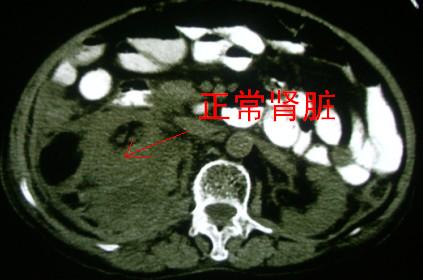

标题: CT6254:续前腹部CT肾脏病变

右侧肾脏内可见混杂密度,可见到低密度脂肪成分,1)右肾血管平滑肌脂肪瘤2)肾癌累积肾周脂肪.不过都要增强

病灶定位在肾外,肾周间隙内,考虑

1肾周的感染

2肾周血肿,建议完善病史,及临床检查

当时也曾考虑,经询问没有外伤史及感染症状.

支持:右肾血管平滑肌脂肪瘤伴出血。

右肾血管平滑肌脂肪瘤伴出血.

考虑:右肾血管平滑肌脂肪瘤,建议增强。

支持肾血管平滑肌脂肪瘤,应该比较典型.